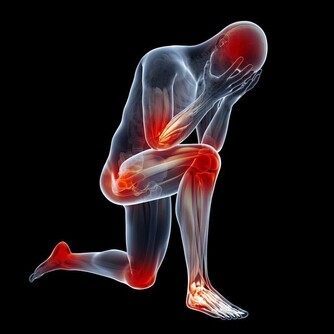

15.自感頭痛、腰痛、身痛,而又查不出器質性的病因。